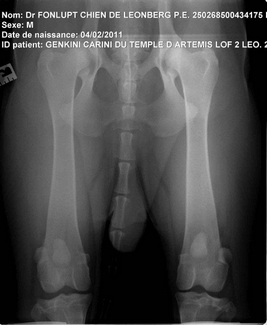

2 très très bonnes nouvelles sont arrivées ! Genkini et Flint'on ont été radiographié et les résultats sont excellents !

Ils sont AA tous les deux, aucun signe de dysplasie coxo-fémorale !